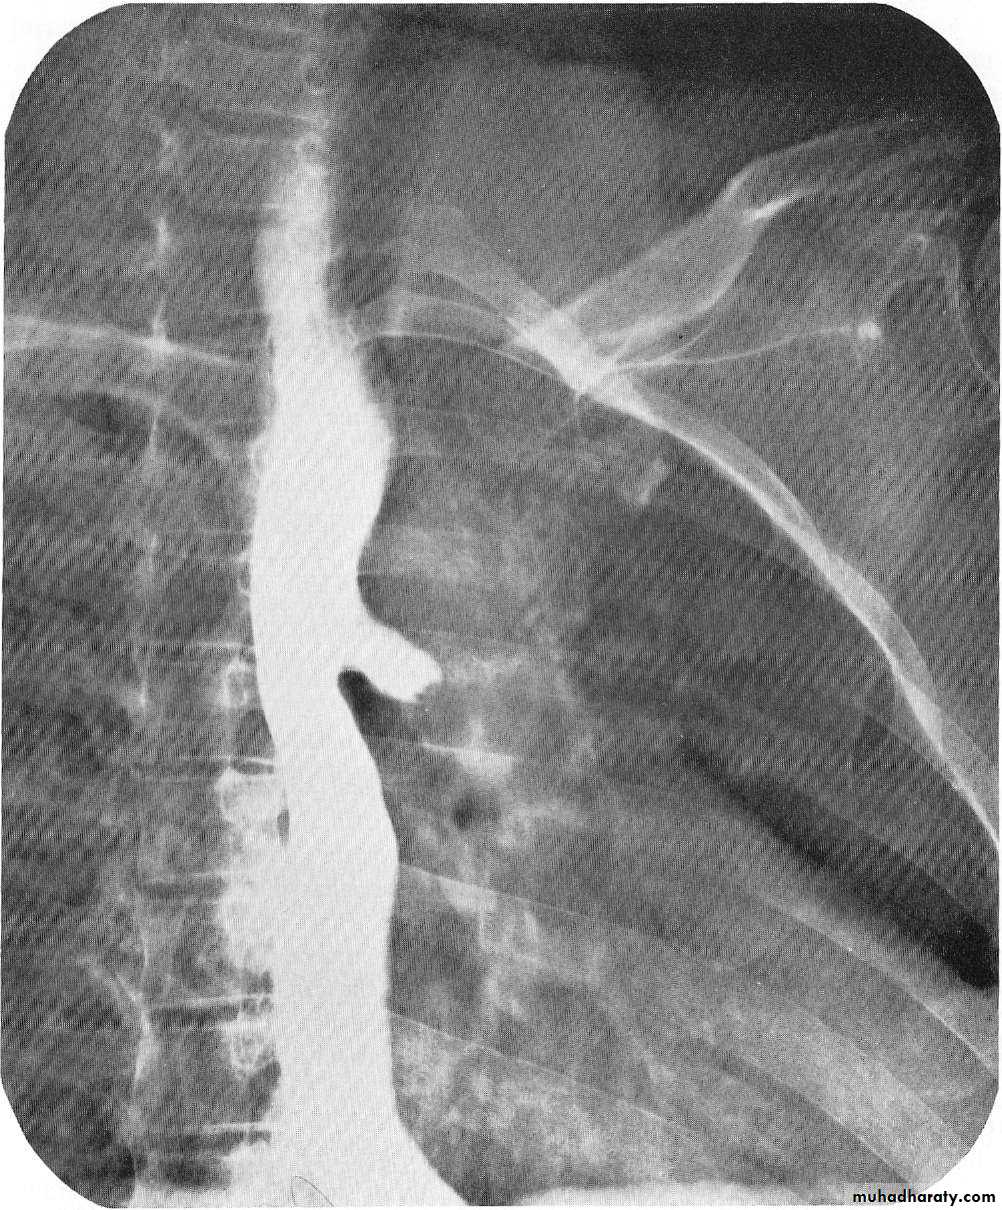

Dilatation

CausesEsophageal atresia

Types:• isolated atresia 8%

• Proximal fistula with distal atresia 1%

• Proximal atresia with distal fistula 85%

• Double fistula with intervening atresia 1%

• Isolated fistula [H-type] 4%